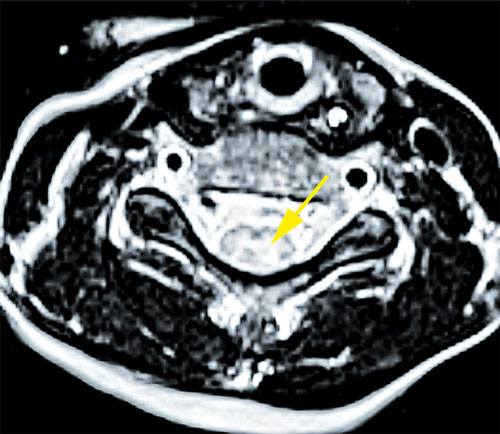

Fall 1. En 9 år gammal flicka sökte på barnakuten efter att ha haft feber i några dagar och vaknat med uttalad svaghet i höger arm. Akut DT-undersökning av hjärna visade normala fynd. Kompletterande MR-undersökning visade signalförändringar i bakre delen av pons och långsträckta signalförändringar i ryggmärgens gråa substans (mer expansiva i halsryggmärgen än i övriga ryggmärgen). Inget patologiskt kontrastmedels­upptag påvisades (Figur 1). MR ingav först misstanke om spinal tumör, men eftergranskning visade en mer tydlig inflammatorisk bild och tumörmisstanken kunde avskrivas. Lumbalpunktion visade lätt pleocytos. Mikrobiologisk utredning i blod och likvor utföll negativ. Prov från feces och nasofarynx togs inte.

Figur 1 (fall 1). Vid initial MR-undersökning visade T2-viktad sekvens expansiva signalförändringar över hela cervikala ryggmärgen (första bilden) jämfört med mer kaudala delar; axialt T2-viktad sekvens i höjd med C4 visade mer expansiv grå substans (andra bilden). T2-viktad FLAIR (fluid attenuated inversion recovery) visade förhöjd signal i bakre delen av pons (tredje bilden). Vid MR-undersökning 10 dagar senare kunde T2-viktad sekvens inte påvisa signalförändringarna i ryggmärgen (fjärde och femte bilden). På T2-viktad FLAIR har signalförändringarna i pons gått i regress (sista bilden).